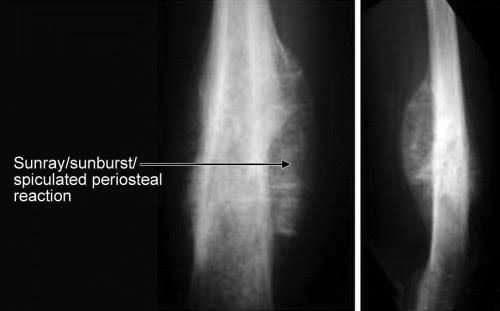

Sunray or sunburst appearance of bone on X-ray: It is the spiculated appearance of the bone as a result of tissue destruction and soft tissue invasion. It occurs as a result of fast growing lesion that don’t give enough time to the periosteum to form a new layer of bone. This condition is seen in malignant condition of bone like osteosarcoma and Ewing’s sarcoma. Picture credit: https://ortholibrary.in/eReader/chapter/9789351526056/ch1